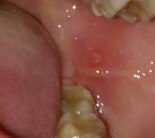

Появилась ранка на щеке. При соприкосновении с чем-либо очень болит. Находится возле зубов, поэтому жевать стало настоящим мучением. Такая же проблема уже была где-то полгода назад на другой щеке. Я полоскала рот антибактериальным средством "Мукосанин" (Беларусь). Вроде прошло через 4 дня. Что-то очень часто меня начинает беспокоить эта проблема: появляются маленькие пузырьки, которые не болят и проходят за день. Но такого болезненного стоматита раньше не было, а сейчас второй раз за полгода. Беспокоюсь, что он и дальше будет появляться.

Как это лечить и что делать, чтобы больше не появлялось?

Прикрепленые фото